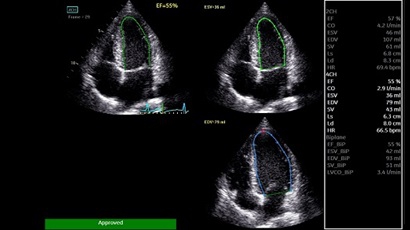

GE VIVID IQ - это передовая портативная система ультразвуковой диагностики, специально разработанная для обеспечения высокого качества образов и мобильности. Благодаря своим компактным размерам и легкому весу, VIVID IQ легко переносится и позволяет проводить УЗИ исследования в различных местах, включая комнаты пациентов, отделения скорой помощи и операционные.

GE VIVID IQ – это ультрасовременный, выполненный в виде ноутбука УЗИ сканер с самым передовым техническим оснащением для проведения диагностических обследований сердечно-сосудистой системы человека. Его особенно оценят бригады скорой помощи из-за малого веса всего 4,5 кг., удобства переноски, а также быстрого выхода из состояния сна для начала работ.

• AUTO 2D EF - режим автоматической недопплеровской количественной оценки глобальной сократительной функции ЛЖ (по Simpson).

• AFI - режим цифровой недопплеровской качественной и количественной оценки региональной сократительной функции ЛЖ.